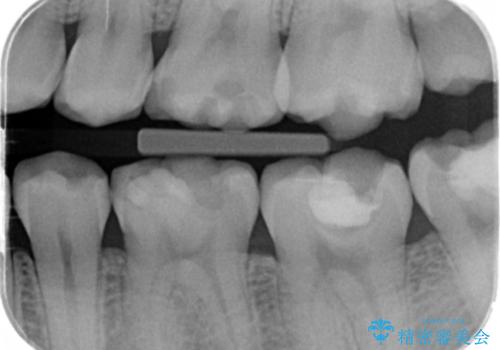

- 奥歯がしみるとのことで来院されました。

検査の結果、古い詰め物の裏側に虫歯ができていること(二次う蝕)が確認されたため、治療していくこととなりました。

虫歯が大きくても、今回のように神経を温存することができる場合があります。